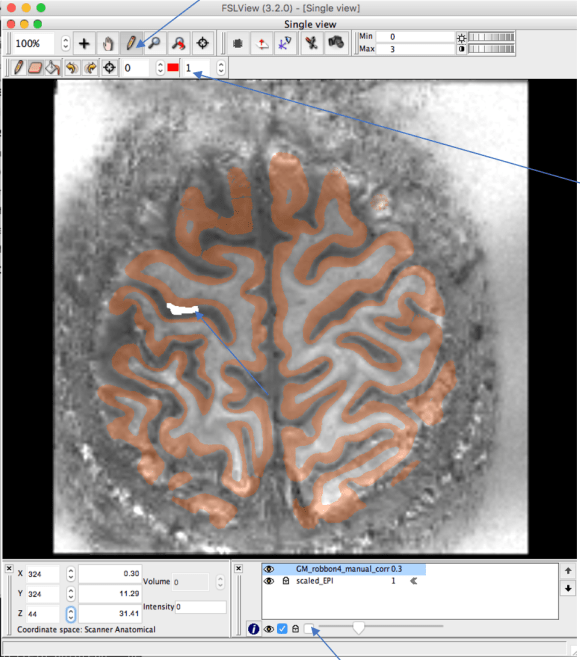

cd subject_name @SUMA_Make_Spec_FS -sid subject_name -NIFTI cd SUMA cp ../../EPI.nii ./ cp ../../warped_MP2RAGE.nii ./ echo "************* upscaling EPI.nii ******************************" module load afni delta_x=$(3dinfo -di EPI.nii) delta_y=$(3dinfo -dj EPI.nii) delta_z=$(3dinfo -dk EPI.nii) sdelta_x=$(echo "(($delta_x / 4))"|bc -l) sdelta_y=$(echo "(($delta_x / 4))"|bc -l) sdelta_z=$(echo "(($delta_z / 4))"|bc -l) echo "$sdelta_x" echo "$sdelta_y" echo "$sdelta_z" 3dresample -dxyz $sdelta_x $sdelta_y $sdelta_z -rmode Li -overwrite -prefix scaled_EPI.nii -input EPI.nii #get obliquity matrix 3dWarp -card2oblique EPI.nii -verb warped_MP2RAGE.nii -overwrite > orinentfile.txt echo "dense mesh starting" #get dense mesh MapIcosahedron -spec subject_name_lh.spec -ld 564 -prefix std_lh.ld564. -overwrite MapIcosahedron -spec subject_name_rh.spec -ld 564 -prefix std_rh.ld564. -overwrite echo "************************ get surfaces in oblique orientation left" ConvertSurface -xmat_1D orinentfile.txt -i std_lh.ld564.lh.pial.gii -o std_lh.ld564.lh.pial.obl.gii -overwrite ConvertSurface -xmat_1D orinentfile.txt -i std_lh.ld564.lh.smoothwm.gii -o std_lh.ld564.lh.smoothwm.obl.gii -overwrite #get spec for the new file quickspec -tn gii std_lh.ld564.lh.pial.obl.gii mv quick.spec std_lh.ld564.lh.pial.obl.spec quickspec -tn gii std_lh.ld564.lh.smoothwm.obl.gii mv quick.spec std_lh.ld564.lh.smoothwm.obl.spec inspec -LRmerge std_lh.ld564.lh.smoothwm.obl.spec std_lh.ld564.lh.pial.obl.spec -detail 2 -prefix std_BOTH.ld564.lh.orient.spec -overwrite echo " **************************" echo " get binary mask of surface left" echo " **************************" 3dSurf2Vol -spec std_lh.ld564.lh.pial.obl.spec -surf_A std_lh.ld564.lh.pial.obl.gii -map_func mask -gridset scaled_EPI.nii -prefix lh.pial.epi_vol.nii -sv T1.nii -overwrite 3dSurf2Vol -spec std_lh.ld564.lh.smoothwm.obl.spec -surf_A std_lh.ld564.lh.smoothwm.obl.gii -map_func mask -gridset scaled_EPI.nii -prefix lh.WM.epi_vol.nii -sv T1.nii -overwrite 3dSurf2Vol -spec std_BOTH.ld564.lh.orient.spec -surf_A std_lh.ld564.lh.smoothwm.obl.gii -surf_B std_lh.ld564.lh.pial.obl.gii -sv T1.nii -gridset scaled_EPI.nii -map_func mask -f_steps 40 -f_index points -f_p1_fr 0.07 -f_pn_fr -0.05 -prefix ribbonmask_564_lh.nii -overwrite # is fill should be bigger #3dSurf2Vol -spec std_BOTH.ld564.lh.orient.spec -surf_A std_lh.ld564.lh.smoothwm.obl.gii -surf_B std_lh.ld564.lh.pial.obl.gii -sv T1.nii -gridset scaled_EPI.nii -map_func mask -f_steps 40 -f_index points -f_p1_fr -0.05 -f_pn_fr 0.05 -prefix ribbonmask_564_lh.nii -overwrite echo " **************************" echo " *******DONE WITH LEFT HEMISHPERE" echo " **************************" echo "************************ get surfaces in oblique orientation left" ConvertSurface -xmat_1D orinentfile.txt -i std_rh.ld564.rh.pial.gii -o std_rh.ld564.rh.pial.obl.gii -overwrite ConvertSurface -xmat_1D orinentfile.txt -i std_rh.ld564.rh.smoothwm.gii -o std_rh.ld564.rh.smoothwm.obl.gii -overwrite #get spec for the new file quickspec -tn gii std_rh.ld564.rh.pial.obl.gii mv quick.spec std_rh.ld564.rh.pial.obl.spec quickspec -tn gii std_rh.ld564.rh.smoothwm.obl.gii mv quick.spec std_rh.ld564.rh.smoothwm.obl.spec inspec -LRmerge std_rh.ld564.rh.smoothwm.obl.spec std_rh.ld564.rh.pial.obl.spec -detail 2 -prefix std_BOTH.ld564.rh.orient.spec -overwrite echo " **************************" echo " get binary mask of surface right" echo " **************************" 3dSurf2Vol -spec std_rh.ld564.rh.pial.obl.spec -surf_A std_rh.ld564.rh.pial.obl.gii -map_func mask -gridset scaled_EPI.nii -prefix rh.pial.epi_vol.nii -sv T1.nii -overwrite 3dSurf2Vol -spec std_rh.ld564.rh.smoothwm.obl.spec -surf_A std_rh.ld564.rh.smoothwm.obl.gii -map_func mask -gridset scaled_EPI.nii -prefix rh.WM.epi_vol.nii -sv T1.nii -overwrite 3dSurf2Vol -spec std_BOTH.ld564.rh.orient.spec -surf_A std_rh.ld564.rh.smoothwm.obl.gii -surf_B std_rh.ld564.rh.pial.obl.gii -sv T1.nii -gridset scaled_EPI.nii -map_func mask -f_steps 40 -f_index points -f_p1_fr 0.07 -f_pn_fr -0.05 -prefix ribbonmask_564_rh.nii -overwrite #3dLocalstat -nbhd 'SPHERE(0.2)' -prefix filled_ribbonmask_564 ribbonmask_564+orig 3dcalc -a ribbonmask_564_rh.nii -b ribbonmask_564_lh.nii -expr 'a + b ' -prefix fill.nii -overwrite 3dcalc -a lh.pial.epi_vol.nii -b rh.pial.epi_vol.nii -expr 'a + b ' -prefix pial_vol.nii -overwrite 3dcalc -a lh.WM.epi_vol.nii -b rh.WM.epi_vol.nii -expr 'a + b ' -prefix WM_vol.nii -overwrite 3dLocalstat -nbhd 'SPHERE(0.3)' -stat mean -overwrite -prefix filled_fill.nii fill.nii 3dcalc -a filled_fill.nii -b fill.nii -expr 'step(step(a-0.5)+b)' -overwrite -prefix filled_fill.nii 3dcalc -a filled_fill.nii -b pial_vol.nii -c WM_vol.nii -expr 'step(a-b-c)' -overwrite -prefix GM_robbon4_manual_corr.nii 3dcalc -a filled_fill.nii -b pial_vol.nii -c WM_vol.nii -expr 'a + b + 2*c ' -prefix rim_auto.nii -overwrite cp filled_fill.nii ../../ cp pial_vol.nii ../../ cp WM_vol.nii ../../ cp rim_auto.nii ../../ cp scaled_EPI.nii ../../ cp GM_robbon4_manual_corr.nii ../../5. manual correction of GM_ribbon.nii

fslview:

- uncheck protection

- use Pen to draw GM AREAS that are miss classified

- Use errasor to remouve GM (almost never happens)

- opposite sides of a sulcus should not touch each other